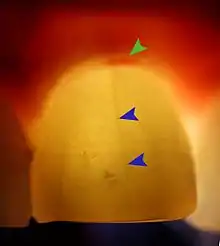

Less commonly used tests might include trans-illumination (to detect congestion of the maxillary sinus or to highlight a crack in a tooth), dyes (to help visualize a crack), a test cavity, selective anaesthesia and laser doppler flowmetry.

Plastic wedge to identify pain on biting from a fractured tooth Transillumination demonstrating fracture

Transillumination demonstrating fracture Decay (green) with apical abscess (blue)